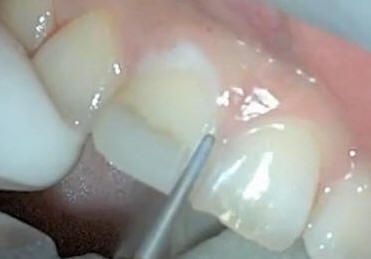

Tallado de las caras

mesial y distal con puntas de diamante troncocónicas de

extremo redondeado |